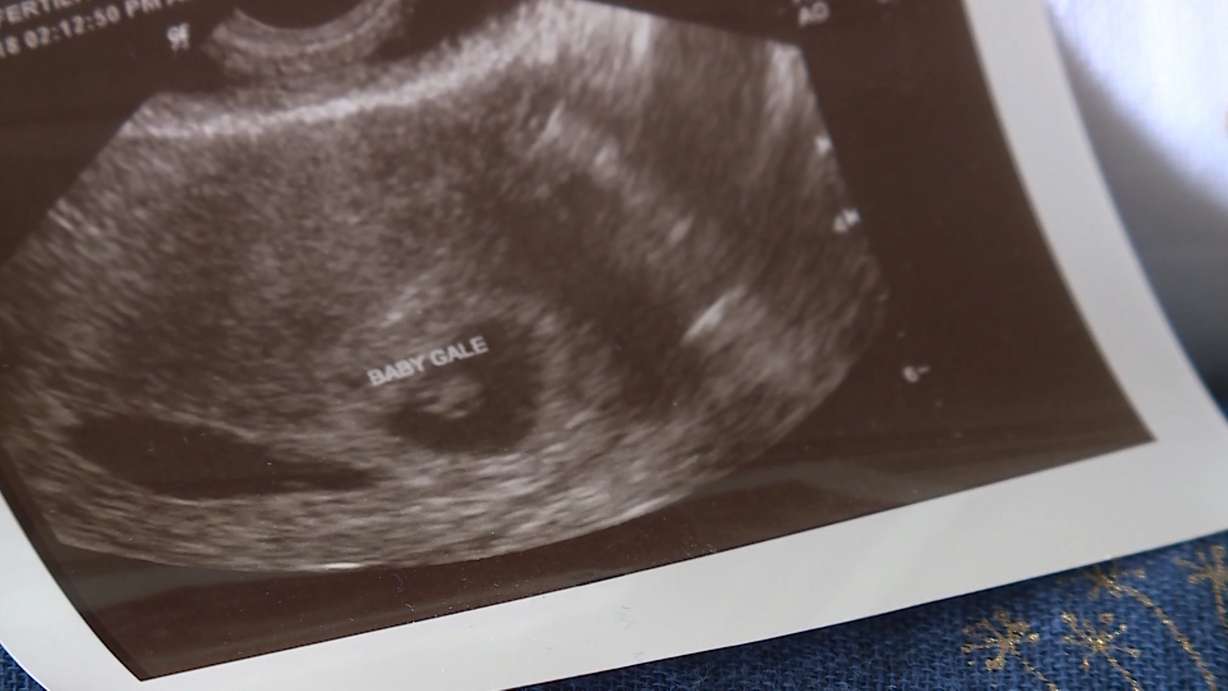

The Gales didn’t waste any time in giving IVF a shot and it worked. She still smiles as she replays the voicemail from the fertility clinic confirming the positive test.

“It’s still so weird,” Gale said. “I feel the baby kicking and it’s like, 'Wow! There is really a baby in there.'”

After 15 years things are looking up, and baby Gale is joining the family in June.